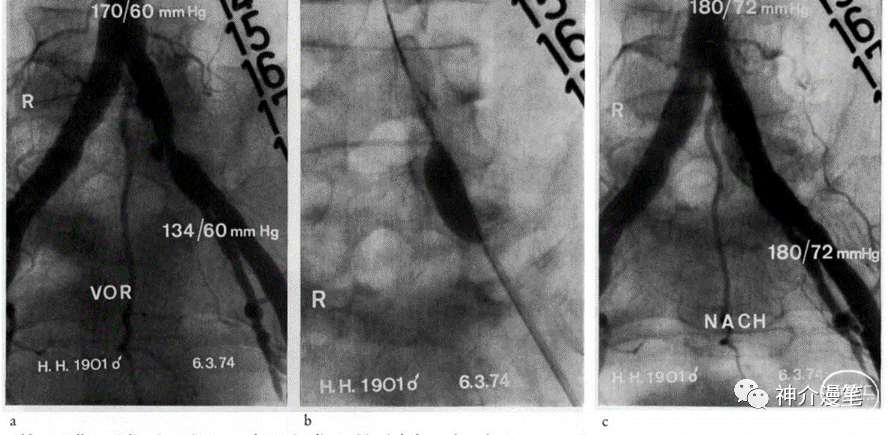

1974年,Gruntzig and Hopf首次报道使用非顺应性球囊扩张下肢动脉狭窄,使得介入治疗真正的进入了一个新的纪元。1977年,Gruntzig 首次报道使用球囊进行冠脉扩张成型术,从此冠脉介入的春天真实的到来了。

1979年,Klaus Mathias在一位32岁的肌纤维发育不良的女性颈内动脉首次进行球扩成型。能抓住这个病例的原因是血管外科认为手术风险不确定而拒绝给这位患者进行手术。操作过程为:猎人头导管陪0.035导丝,到位后交换4*40球囊,无导引导管等支撑。人类史上首次的颈动脉球囊扩张术诞生了。1980年,他首次给一名68岁的粥样硬化性狭窄患者进行球扩成型术中没有造影指引,根据骨性标志“盲扩”。手术效果都很不错,可以说是技惊四座。